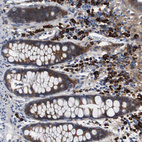

Immunohistochemical staining of human cerebral cortex shows strong granular cytoplasmic positivity in neurons.